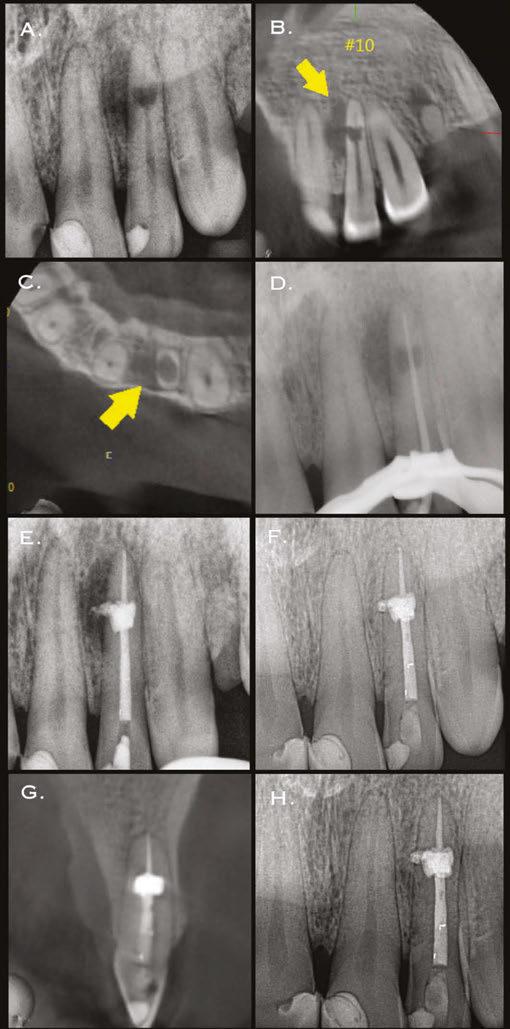

Case report 2

A 56-year-old male presented with a chief complaint of vague discomfort in the left mandible. The patient reported that the discomfort had been intermittent for more than 6 months but

Figures 3A-3H: 3A. Preoperative periapical radiograph of tooth No.10 showing internal root resorption in apical third of root. There is significant alveolar bone loss adjacent to defect. 3B. Sagittal CBCT image of tooth No. 10 showing internal resorptive defect perforating on mesial aspect of root. Note adjacent alveolar bone loss extending proximally to tooth No. 9. 3C. Axial CBCT image of internal resorptive defect perforating on mesial aspect of root. There is thin layer of circumferential dentin remaining and extensive alveolar bone loss adjacent to the defect. 3D. Periapical radiograph showing gutta-percha cone fit. Gutta-percha cone passes through resorptive defect to contact apical portion of root canal. 2E. Immediate postoperative periapical radiograph of tooth No.10 once root canal was completed and resorptive defect was restored. 2F. Two-year follow-up showing complete healing of radiolucency adjacent to defect and reestablishment of PDL. 2G. Two-year follow-up CBCT. Coronal slice showing complete healing of radiolucency adjacent to defect and reestablishment of PDL. 2H. Five-year follow-up radiograph. Patient is completely asymptomatic

Figures 4A-4H: 4A. Preoperative periapical radiograph of tooth No. 19. Visualization of periapical radiolucency associated with mesial root is possible. Root also appears to be calcified in middle and apical thirds. 4B. Sagittal CBCT slice showing internal resorption in apical portion of mesial root. Visualization of resorptive defect perforating on distal aspect of mesial root, and significant periapical pathology extending close to furcation is possible. Defect and extent of pathology was not visualized on periapical radiograph. 4C. Axial CBCT slice showing resorptive defect encapsulating both MB and ML canals and perforating on distal aspect of mesial root. There is significant bone loss adjacent to perforating defect. 4D. Coronal CBCT slice showing internal resorptive defect encapsulating both mesiobuccal and mesiolingual canals. 4E. Immediate postop radiograph after completion of endodontic treatment. 4F,4G. Coronal and axial CBCT slice at 16-month follow-up. Note resorptive defect filled with bioceramic sealer and complete healing of adjacent bone and reestablishment of PDL. Patient returned at 16-month point for endodontic treatment of tooth No.18. 4H. Three-year follow-up radiograph. Patient remained completely asymptomatic on tooth No 19

had recently worsened. Clinical examination revealed pain to percussion on tooth No. 19. No swelling was observed, and the tooth was not sensitive to palpation or biting. Radiographic and CBCT (Veraviewepocs 3D R100; J. Morita) examination revealed a crowned tooth No.19 with perforating internal root resorption near the apical end of the mesial root, accompanied by periapical pathology extending distally to involve the distal root and coronally toward the furcation (Figures 4A-4D). A diagnosis of pulpal necrosis with symptomatic apical periodontitis was made.

The prognosis for treating the tooth with root canal therapy was discussed, along with alternative options such as extraction and replacement with an implant or bridge. Due to financial constraints, the patient opted for endodontic treatment rather than extraction. It was also explained that follow-up treatment, including an apicoectomy of the mesial root, might be necessary if the lesion persists. Informed consent was obtained.

First visit

The patient was anesthetized with 1.7 mL of 3% mepivacaine (Carbocaine, Dentsply Pharmaceutical, York, Pennsylvania) via left inferior alveolar nerve block and 1.7 mL of 4% articaine with 1:100,000 epinephrine (Septocaine; Septodont, Lancaster, Pennsylvania) via buccal infiltration. After achieving rubber dam isolation, access was made through the porcelain-fused-to-metal (PFM) crown using a combination of a round diamond bur and a No. 2 surgical length carbide round bur. Necrotic pulp was encountered. Working length was established with a Root ZX apex locator (Morita, Tokyo, Japan). The canals were instrumented to a size 35 .04 Vortex Blue rotary file (Dentsply Tulsa Dental, Johnson City, Tennessee) and irrigated with 5.25% sodium hypochlorite. The EndoActivator (Dentsply, Tulsa, Oklahoma) was used to sonically agitate the irrigant to ensure thorough disinfection of the resorptive defect. The canals were dried with paper points, and calcium hydroxide (Ultracal XS, Ultradent Products Inc, South Jordan, Utah) was syringed into the canals and defect. The tooth was then temporarily restored with Cavit (3M ESPE, Neuss, Germany).

Second visit

The patient returned after 3 weeks for completion of endodontic treatment. He reported that all symptoms had subsided. Calcium hydroxide was removed from the canals with instrumentation, irrigation, and activation with the EndoActivator. The canals were dried with paper points, and excess irrigant was removed using a surgical suction with a micro-tip. The canals were coated with BC sealer to allow for sufficient amounts of sealer to fill the resorptive defect and were then obturated with gutta percha and BC (bioceramic) sealer using the technique of warm vertical conden-

sation (Figure 4E). The occlusal access opening was restored with TPH Spectra ST composite (Dentsply Sirona, Charlotte, North Carolina), and the patient was put on a recall schedule to monitor healing. The patient returned at the 16-month point for endodontic treatment of tooth No. 18. At a 16-month recall visit, the patient was completely asymptomatic on tooth No.19. And radiographic/CBCT examination revealed complete healing of the lesion adjacent to the resorptive defect on tooth No. 19 (Figures 4F and 4G). At the 3-year recall, the patient was asymptomatic on both teeth Nos.18 and 19.

Conclusion

Two cases of extensive perforating internal root resorption (IRR) successfully treated nonsurgically are presented. A discussion of the biologic process of IRR, combined with the importance of accurate diagnosis, underscores that a nonsurgical approach should be the primary treatment plan in such cases. The advent of bioceramic sealers has enabled a more standardized and effective endodontic approach for managing perforating internal resorption. Additionally, the use of CBCT during the diagnostic planning phase is crucial for accurately visualizing the full extent of the lesion.